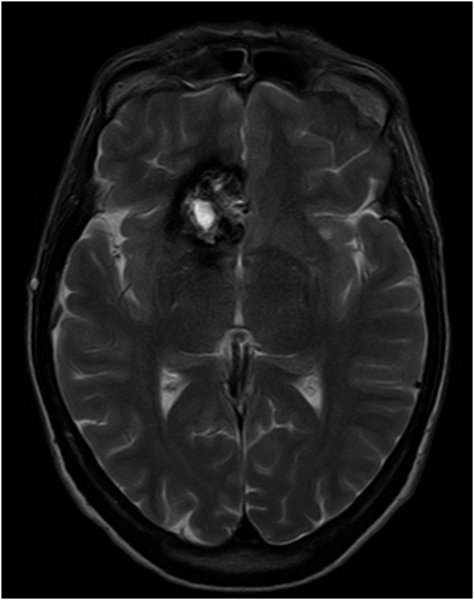

Kavernom - T2 axial

Charkateristische Haemosiderinabbauprodukte in Form

von hypointensen Signalalterationen